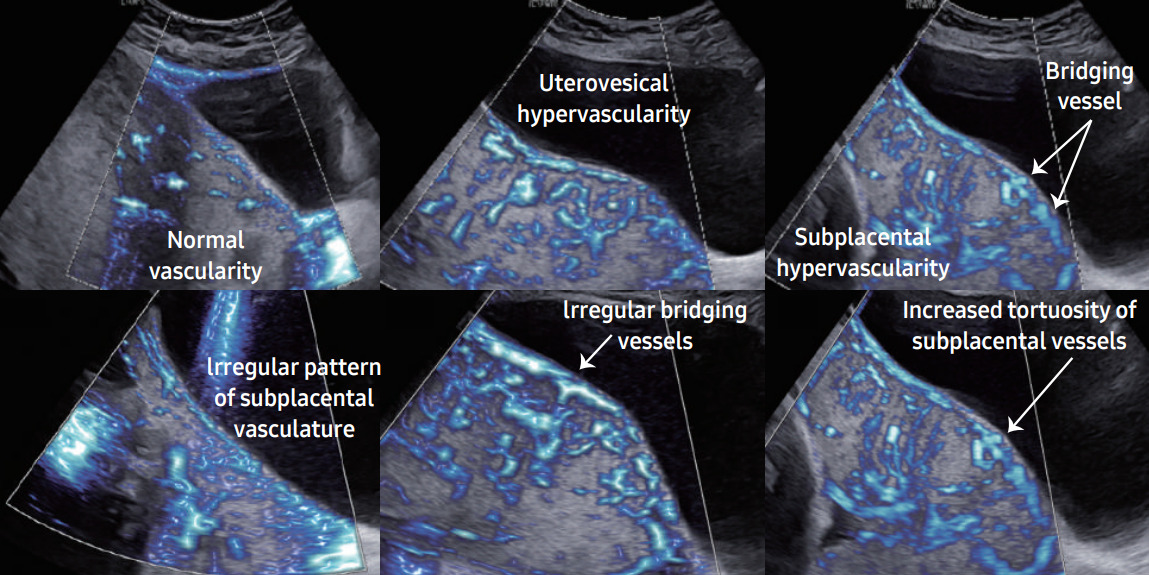

Другой способ оценки, визуализации и диагностики Placenta accreta spectrum (PAS) в системах Samsung использует аномальную гиперваскуляризацию и сложные сосудистые сети в плаценте, параметрии и маточно-пузырном интерфейсе. MV-Flow и LumiFlow — это недавно разработанные допплеровские технологии, способные обеспечить детальное представление о кровотоке по отношению к окружающим тканям в качестве альтернативы энергетическому допплеру для визуализации микроциркуляторных структур с медленным кровотоком сосудистых соединений.

Технология MV-Flow характеризуется высокой степенью уменьшения сигналов тканевого шума, подавлением артефактов вспышки, составными изображениями и высокой чувствительностью. Все это способствует оптимизации визуализации структур с низкой скоростью потока. LumiFlow помогает интуитивно отображать структуру кровотока и мелких сосудов, обеспечивая псевдотрехмерную визуализацию кровотока в двухмерном изображении за счет стереоскопического эффекта. Эта функция высокого разрешения доступна в сочетании со всеми допплеровскими технологиями, позволяющими реалистично оценивать сосудистый поток. Такие технологии могли бы помочь в визуализации сосудистых сетей на маточно-пузырной границе, параметрии и плаценте.